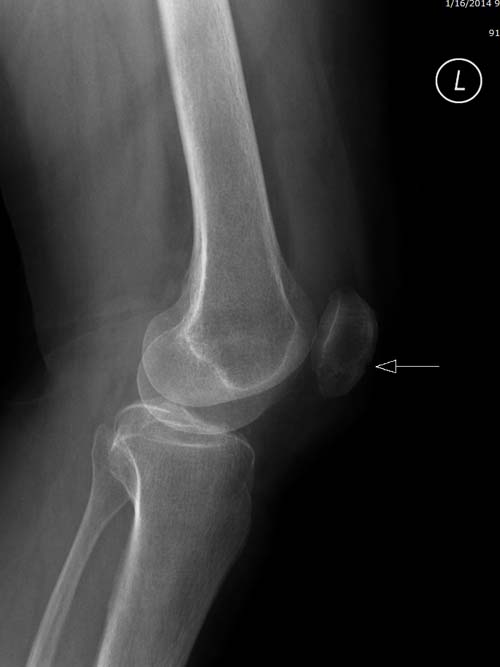

Re: Импрессионный перелом латерального мыщелка левой большеберцевой кости.

Если следовать принципу "контрактура спасет от боли", можно и загипсовать. Я бы препочел под контролем глаза через контралатеральное окно имппктором выдавить суставную площадку на место. Заполнить образовавшийся канал спонгиозным или искусственным графтом. Для опоры субхондрально провести два 3,5 мм винта.

Устранение импрессии, костная аутопластика, остеосинтез опорной пластиной

оперировать вероятнее всего надо, импрессия приличная , думаю около 1,5 см, только вот она в задних отделах, преимущественно. Если ставить опорную пластину, то делать это нужно сзади, иначе никакой опорности, а задний котртекс по КТ похоже замят

Учитывая, что у пациента молодой возраст(судя по рентгенограммам,абсолютно показано восстановление суставной линии: подменисковый доступ,подъём импренированной части мыщелка, костная аутопластика, остеосинтез, решение вопроса с мениском (шов либо парциальная резекция)).